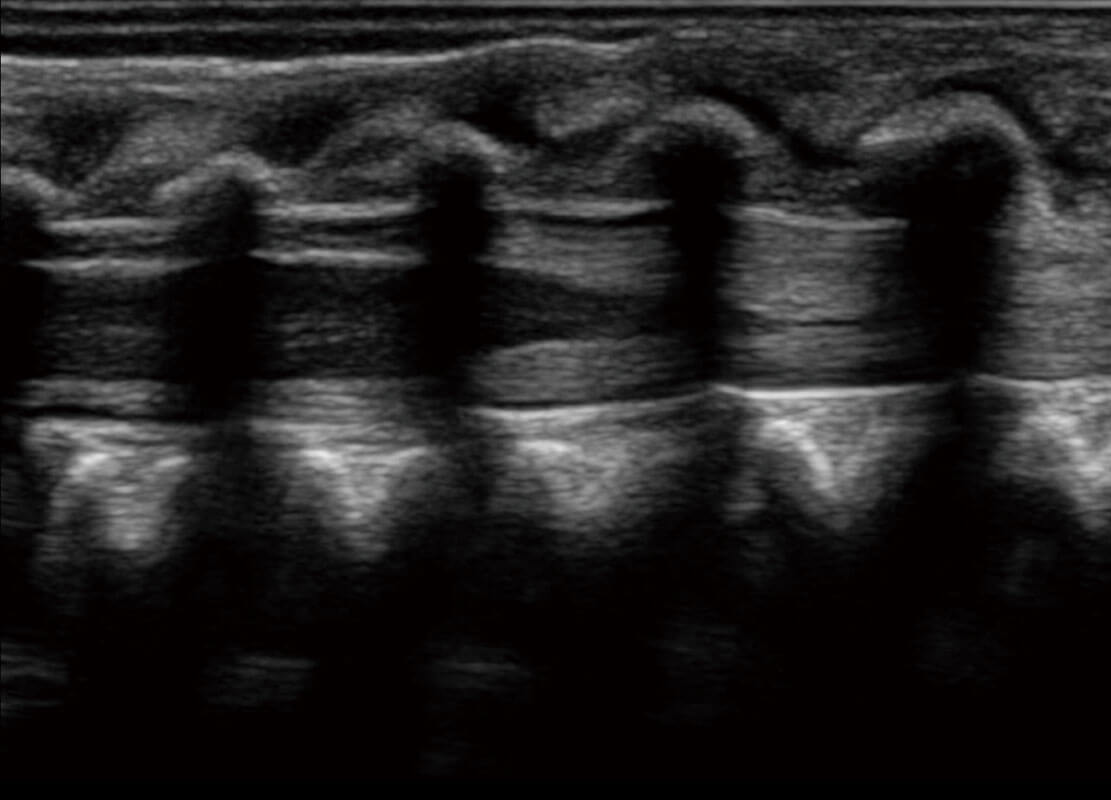

• 新生儿心脏